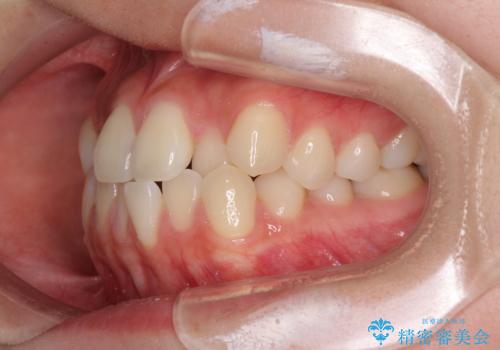

- 前歯のクロスバイトが気になり、インビザラインによる矯正治療を希望して来院された患者様です。

上顎側切歯(上の真ん中から2番目の歯)が舌側転位している場合、インビザラインでは仕上げきれないことが多く、更には無理して動かそうとすると歯髄壊死を起こすリスクが高いと言われています。

インビザラインで歯列を移動する前に、上顎前歯をワイヤー矯正で整え、その後上下歯列をインビザラインにて矯正治療を行うこととしました。

舌側転位している側切歯特有の、切縁の位置が不揃いであったり、根元が内側に引っ込んだ状態であったりという、インビザライン独特の仕上がりになることなく、きれいに整った歯列とすることができました。